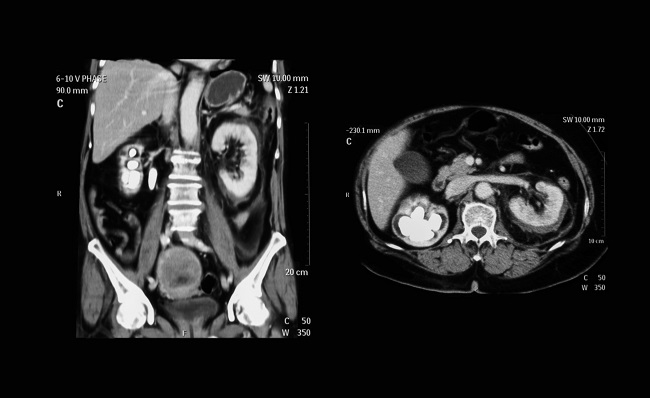

CT scan abdomen adalah pemeriksaan radiologi yang digunakan untuk mengevaluasi rongga abdomen dan organ intraabdomen apabila dicurigai terdapat tumor, perdarahan intraabdomen, ataupun infeksi. CT scan memanfaatkan sinar X dan sudah menjadi bagian esensial dalam penegakan diagnosis dan pengambilan keputusan klinis.[1]

CT scan abdomen dapat bermanfaat dalam berbagai skenario klinis, termasuk penegakan diagnosis tumor intra abdomen, aneurisma aorta abdominalis, ataupun infeksi seperti abses apendiks. CT scan abdomen juga dapat bermanfaat mendeteksi kerusakan pada rongga intraabdomen, seperti ruptur ginjal dan ruptur limpa, serta adanya batu seperti pada nefrolithiasis dan kolelitiasis.